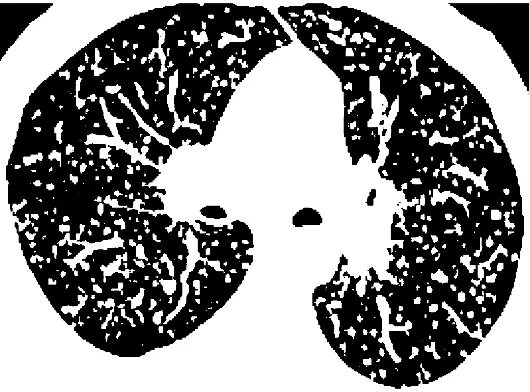

Метатуберкулезные изменения в легких что это означает